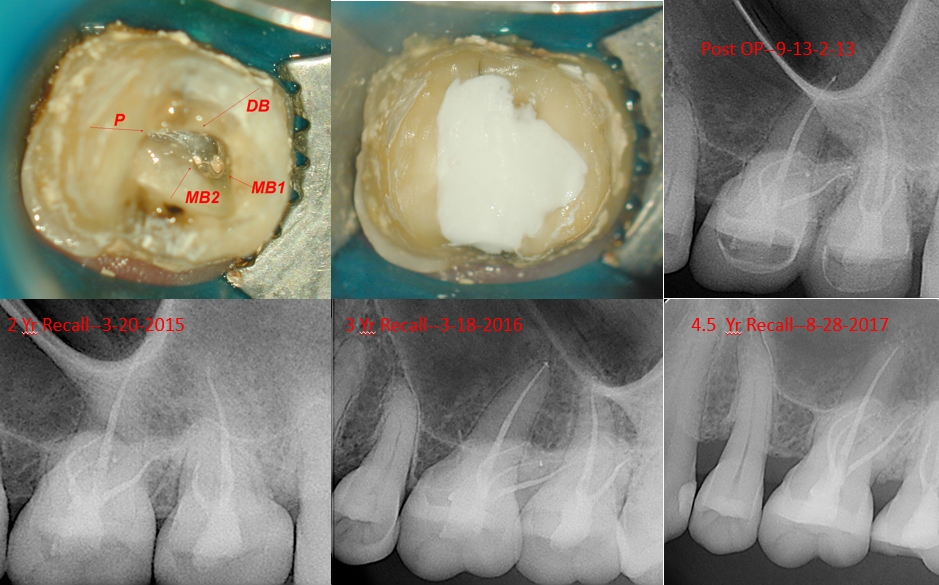

This patient was referred to me by the Prosthodontist next door for evaluation on teeth #14 and 15 prior to crown fabrication. My examination revealed signs consistent with reversible pulpitis. I asked the RD to prep the teeth, temporize and have me re-evaluate. If the symptoms worsened, I would perform endodontic treatment on one, or both teeth. Patient returned three months later, with excruciating pain in both of her molars. Treatment was initiated and completed two weeks later. I love the photograph of the vascular system when I opened tooth #14, looks cool!

the buccal canals were shaped to a 17/.04 VTapers, and the palatal to a 20/.06 VTaper. I saw the patient for a 6MO Recall, a one year recall, and 2,3,4.5 year recall (she missed her 4 year recall) and I should be seeing her in a few months for her 5.5 year recall (I hope the tooth is still there and is still asympomatic).